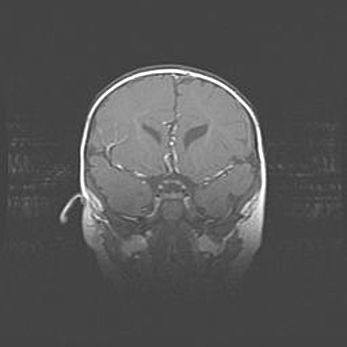

Наружная гидроцефалия с возможной атрофией височных областей.

Возраст: 28 дней

Вес: 3670 г

Пол: мужской

Окружность головы: 38 см

Срок гестации: 40 недель

Гидроцефалия головного мозга у новорожденных – это заболевание, которое характеризуется скоплением избыточного количества спинномозговой жидкости в желудочковой системе головного мозга в результате затруднения её перемещения от места выработки к месту поглощения в кровеносную систему или вследствие нарушения абсорбции. При открытой наружной форме гидроцефалии у новорожденных расширяются и переполняются субарахноидные пространства.

При нормотензивных  формах,  которые,  как  правило,  являются  следствием  перенесенных ишемических  повреждений  паренхимы  мозга,  возможно  сочетание микроцефалии  с нормотензивной гидроцефалией. В основе данных изменений лежит атрофия больших полушарий с преимущественной  локализацией  в  лобно-височных  областях.